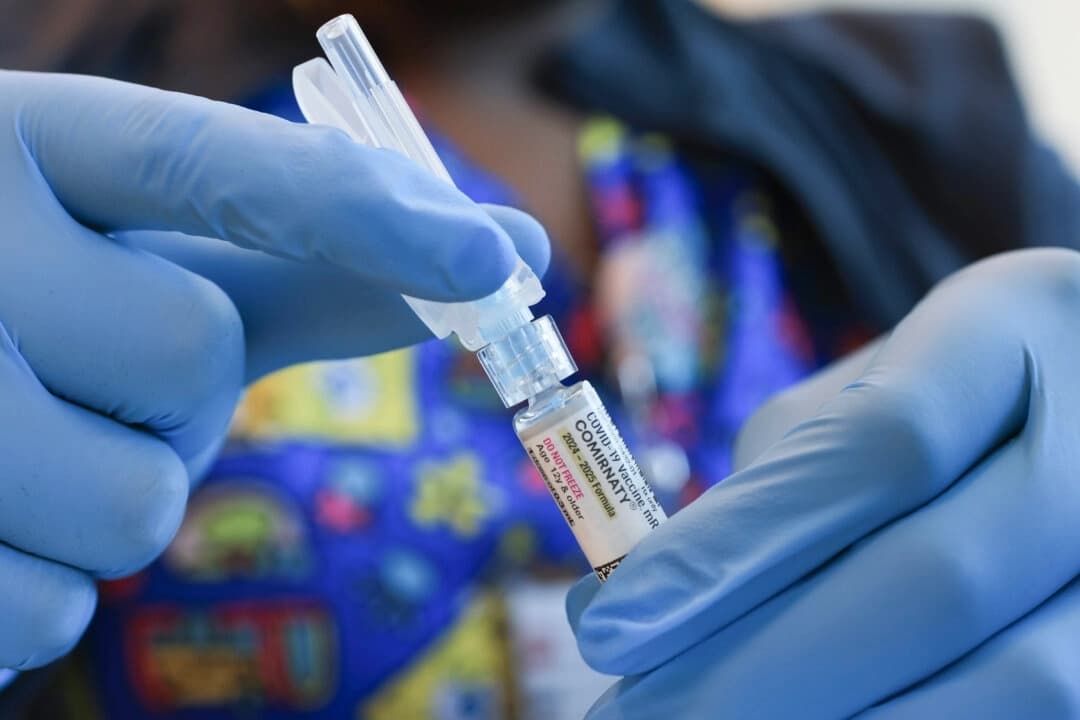

Vacunas y Seguridad

Las vacunas pueden causar autismo, dice agencia de salud pública de EE. UU.

Director interino de los CDC pide a los fabricantes que distribuyan la vacuna MMR en dosis separadas

Menos de la mitad de los adultos consideran que vacuna contra COVID es segura durante embarazo: encuesta

Los CDC dicen que la vacunación contra COVID-19 ahora depende de cada individuo

Menos de la mitad de los adultos consideran que vacuna contra COVID es segura durante embarazo: encuesta

La FDA está considerando evaluar de forma independiente vacunas contra COVID por contaminación de ADN